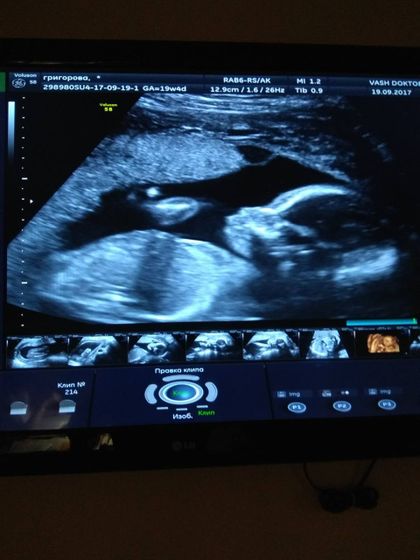

Любимые мои… я уже с УЗИ… и нас меня в животике ростет маленькая, здоровенькая ДЕВОЧКА!??? Я так счастлива!!! Уходила с улыбкой на лице… муж на седьмом небе от счастья и восторга ???уже всем обзвонил… Хорошего Всем Дня любимые мои беременяшки…